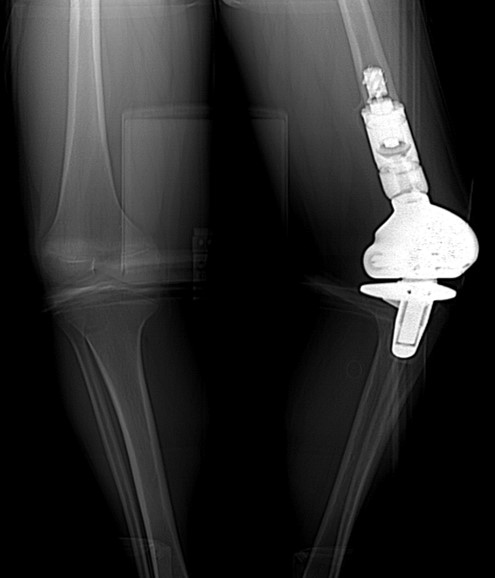

15 year-old girl with history of osteosarcoma of left femur status post resection and prosthesis. Lateral (A) and AP (B) radiographs of the left knee show a distal femur limb sparing prosthesis and knee arthroplasty. |

| 15 year-old girl with history of osteosarcoma of left femur status post resection and prosthesis. Lateral (A) and AP (B) radiographs of the left knee show a distal femur limb sparing prosthesis and knee arthroplasty. |

15 year-old girl with history of osteosarcoma of left femur status post resection and prosthesis. Tc99m whole body bone anterior (C) and posterior (D) projections at different window settings demonstrate mild diffuse increased radiotracer activity around the distal end of the femur prosthesis and proximal end of tibial prosthesis, representing reparative bony remodeling. This can last for many years and is not pathological unless patient complains of new pain in which case one should consider loosening, infection, or recurrence of tumor. |